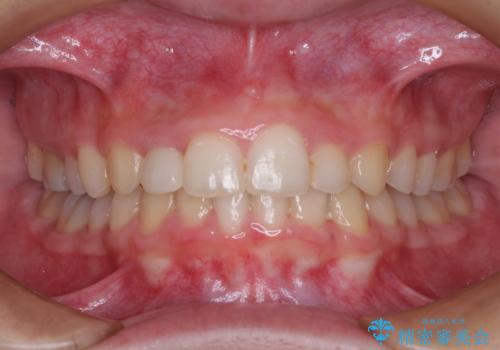

- 前歯の開咬と、受け口による咬み合わせの悪さを気にして来院された患者様です。

左上は後続永久歯の欠損によりスペースがあり、矯正治療と並行してインプラントあるいはブリッジによる補綴治療が必要な状況でした。

上顎歯列が狭窄していたため、急速拡大装置により上顎骨を側方に拡大し、その後インビザラインにて矯正治療を行うこととしました。